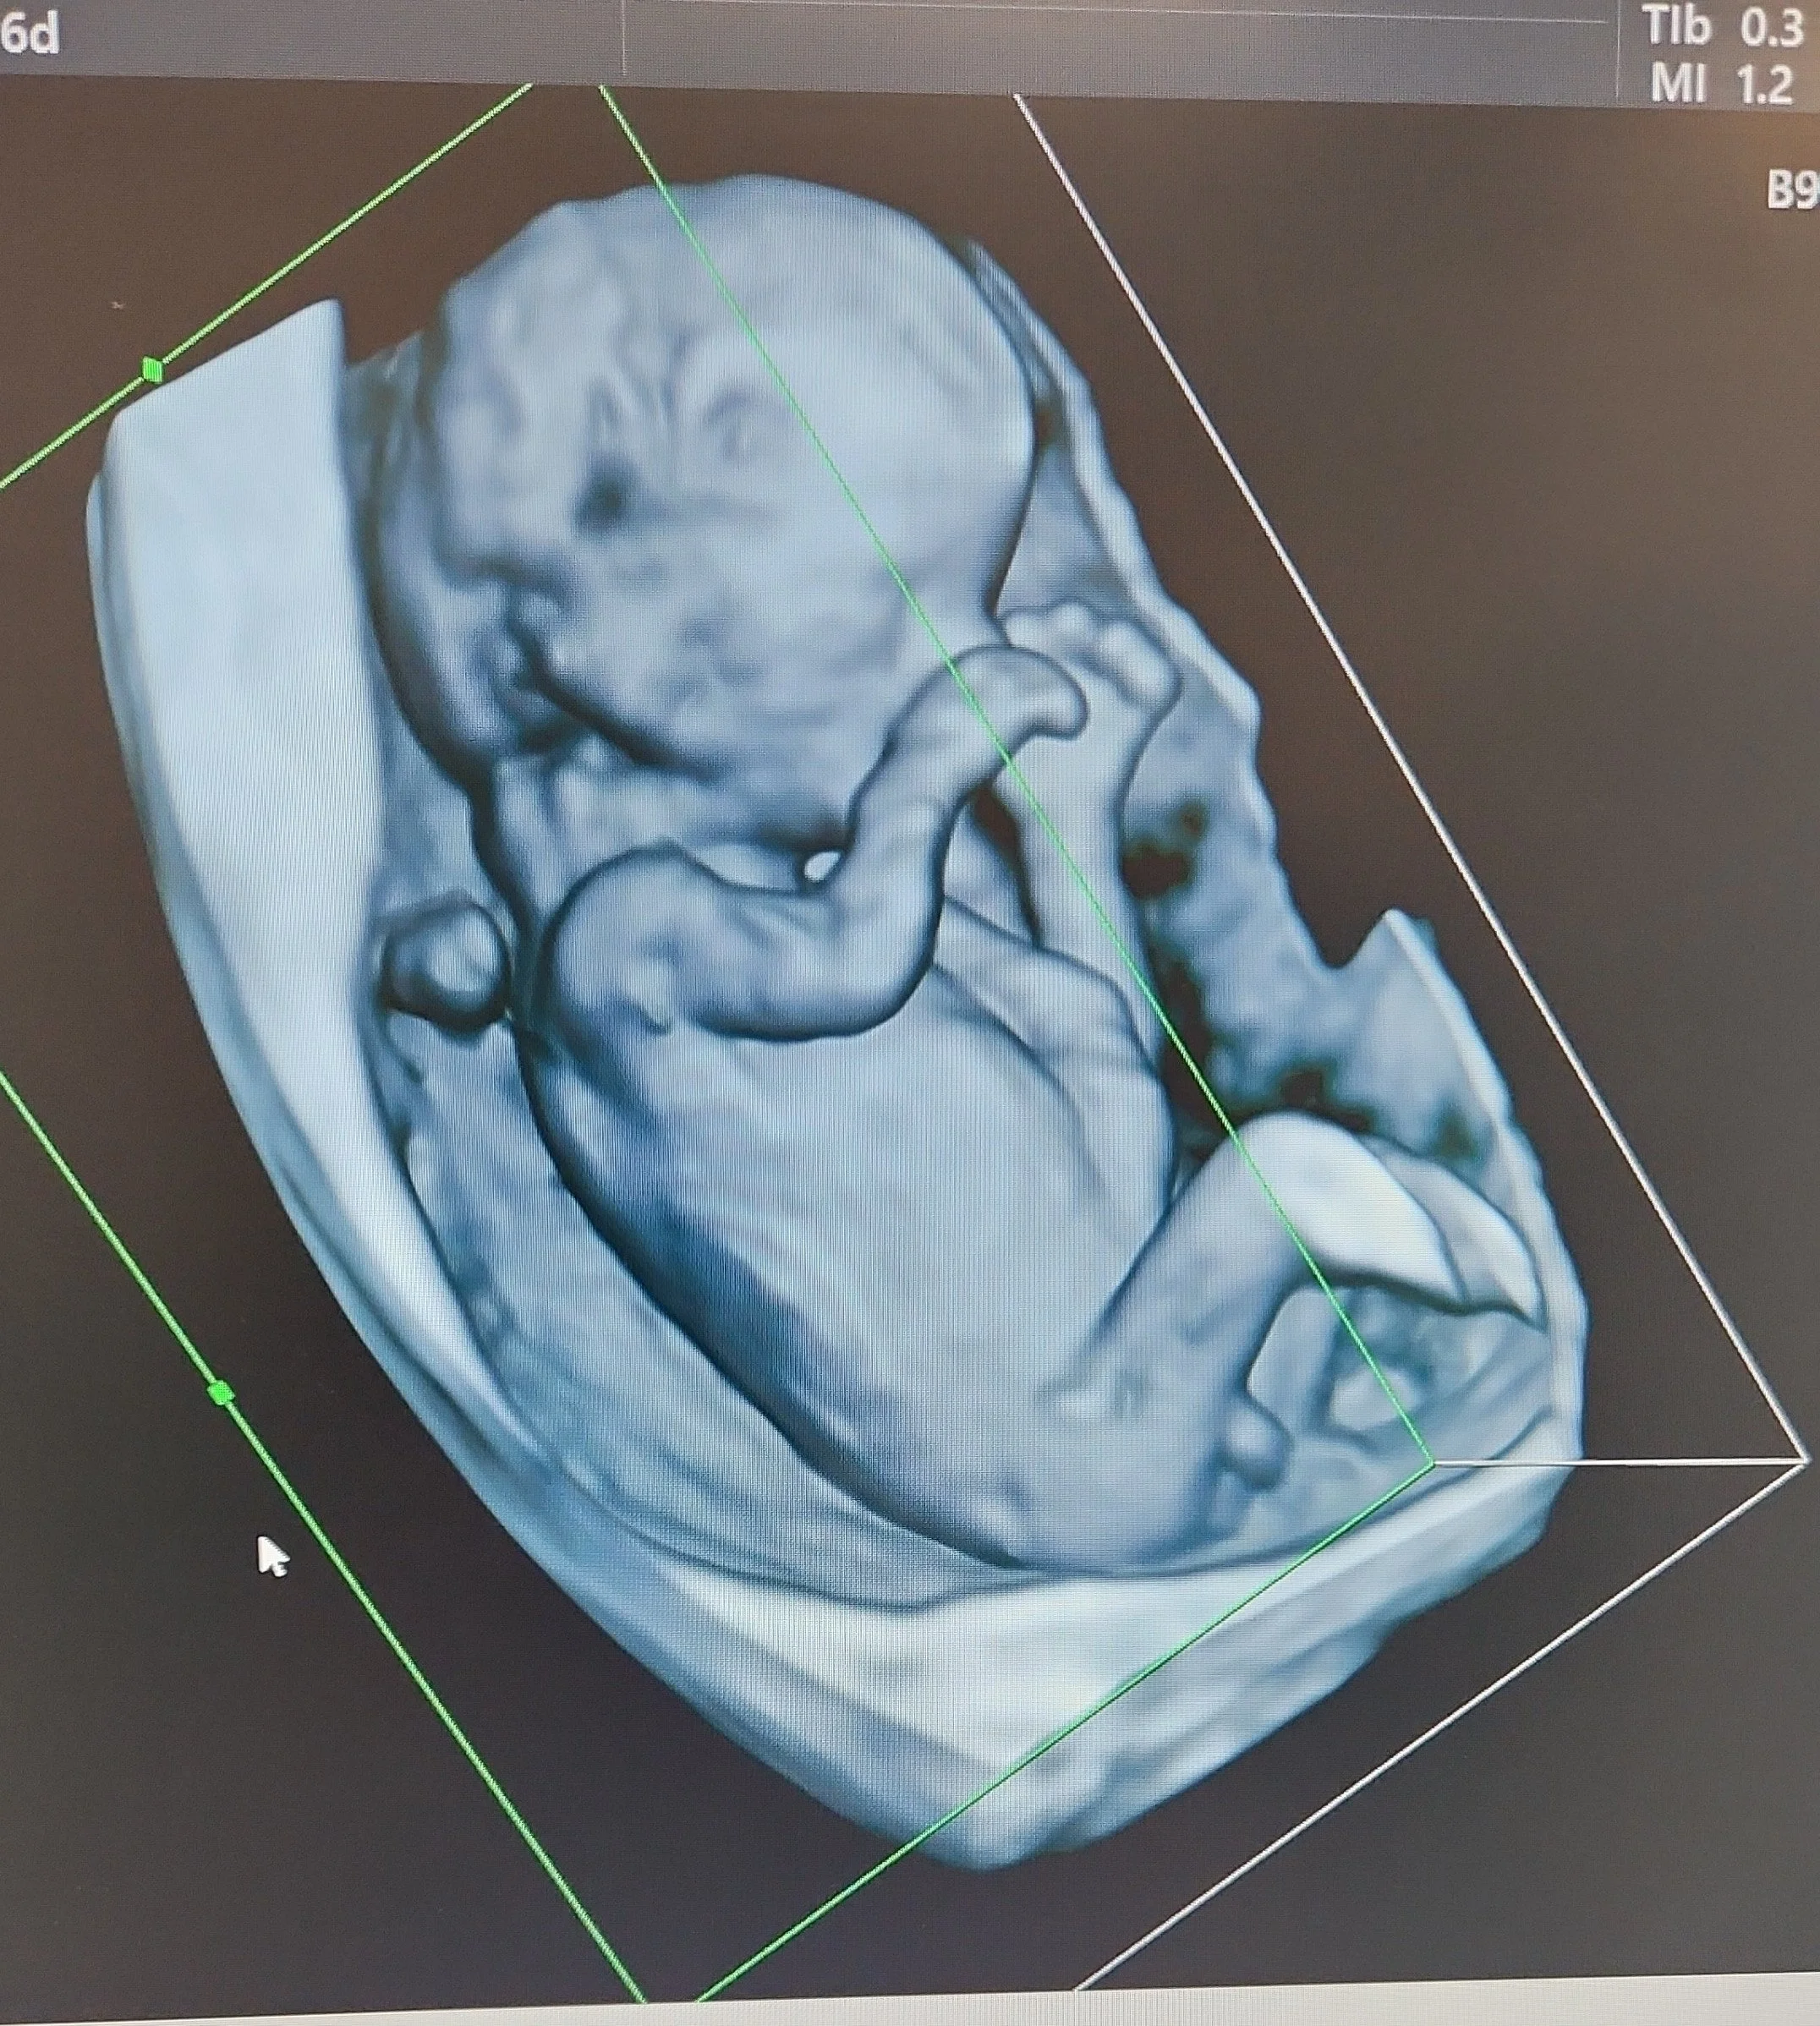

Cette échographie détaillée est réalisée entre 21 et 24 semaines d’aménorrhée. Le foetus pèse alors environ 400 à 600 grammes. C’est le moment idéal pour examiner en détail ses organes et vérifier leur bon développement. Le sexe foetal peut être révélé aux parents s’ils le souhaitent, et certaines malformations peuvent être dépistées.